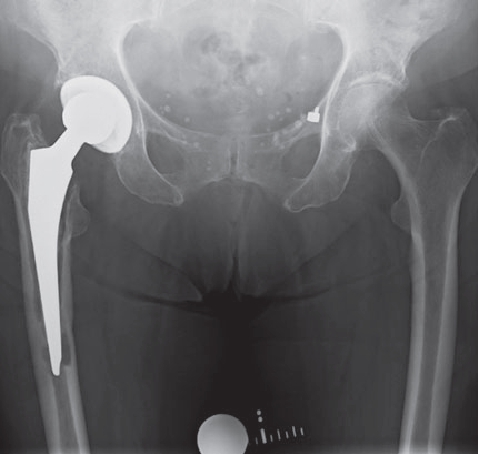

Generally, a distinction is made between acute and chronic infection. A form of chronic infection, the so-called low-grade infection, can also be the reason for premature loosening of the prosthesis. Since the bacteria multiply slowly, this infection is so weak that it is hardly noticed by the patient and also eludes laboratory tests, since it causes hardly any changes in the blood.

In order to diagnose these infections, tissue samples are taken from the joint in addition to a puncture, as only close cooperation between orthopedists, pathologists and microbiologists can ensure the correct diagnosis. In addition, we also devote ourselves to obviously infected prostheses, of course. These infections can occur shortly after the operation (so-called early infection up to 6 weeks postoperatively) but also years after the operation (as so-called late infection). In addition to the smallest entry points (e.g. an ulcerated toenail), serious infections such as pneumonia can also lead to bacteria colonizing the surface of the prosthesis. Patients with a limited immune system (e.g. diabetics, rheumatics) are particularly at risk. If an infection is noticed early enough after surgery, it is occasionally still possible to eliminate the infection without removing the prosthesis by carefully cleaning the wound and changing the moving parts.

However, infections often go unnoticed for many weeks, so that removal of the prosthesis is unavoidable. Depending on the pathogen and its sensitivity, a placeholder containing antibiotics is then implanted, which remains in place for 6 weeks. Antibiotics in tablet form must then also be taken for this period. However, it is not necessary for a patient to remain in the hospital during this entire period. If home care is not possible, for example, it is also possible to organize this in close cooperation with our social services. After 6 weeks it is generally possible to reimplant a prosthesis, provided that the blood values show that the infection is under control. Antibiotics must then be taken again for 6 weeks after surgery. Which antibiotics are taken is determined in close cooperation with colleagues in microbiology and clinical pharmacology, with whom regular rounds and therapy checks are carried out. These therapeutic measures are carried out in a special area of the clinic using the most modern methods.